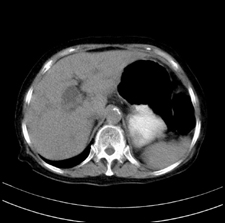

患者,女,75岁。腹痛,体黄5日,膝胸位时腹痛缓解。肝功能明日出来。彩超提示胆总管占位,未见血流信号。心电图提示s-t段改变。患者体质较弱,未能增强。

胆总管上段,腔内有软组织密度影 ,ct值36-44hu。大家看有没有胆管癌的可能。

典型胆总管多发结石;增强扫描前后ct值是否发生改变是鉴别结石与占位的依据。